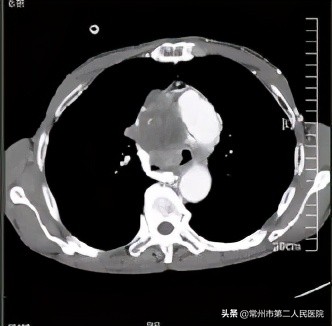

据了解,王大爷一个月来反复出现咯血,气喘的症状也越发严重,被家人送到常州二院就诊。“我们经过检查发现,患者的气管隆突部,也就是气管最下端和两侧主支气管的连接点处存在一肿块,肿块向左、右主支气管腔生长,导致双侧支气管明显狭窄。另外,他的右上纵隔内多数淋巴结肿大,融合也形成了一个乒乓球般大小的肿块,使上腔静脉明显受挤压。收治入院后经过一系列的治疗,他气喘的症状得到了一定的缓解。”常州二院呼吸与危重医学科主任俞小卫介绍道。

(上腔静脉明显受挤压,如图)